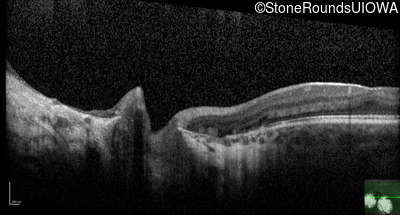

Age at visit: 2 months (Visit 3)

Age at visit: 2 months (Visit 4)